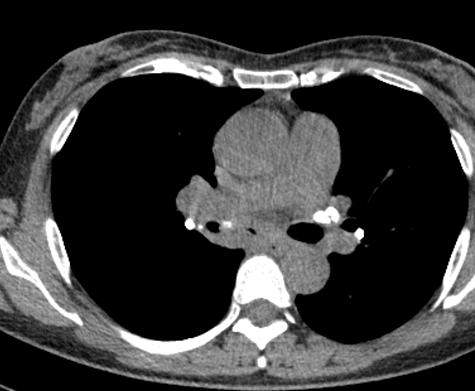

另外,这个患者的钙化灶非常危险,因为钙化灶的一端距离肺动脉才2毫米左右(图17),支气管镜下强行牵拉钙化病灶很可能会大出血危及生命。

图17 胸部CT

明确诊断及治疗都需要支气管镜检查,肿么办?改全麻下行硬质支气管镜检查。

术中见右中间支气管有灰褐色、坚硬、异物样病灶,病灶的根部嵌顿在支气管内(图18),用异物钳不能取出病灶(注意,不能强行牵拉钙化灶,会撕裂血管引起大咯血)。